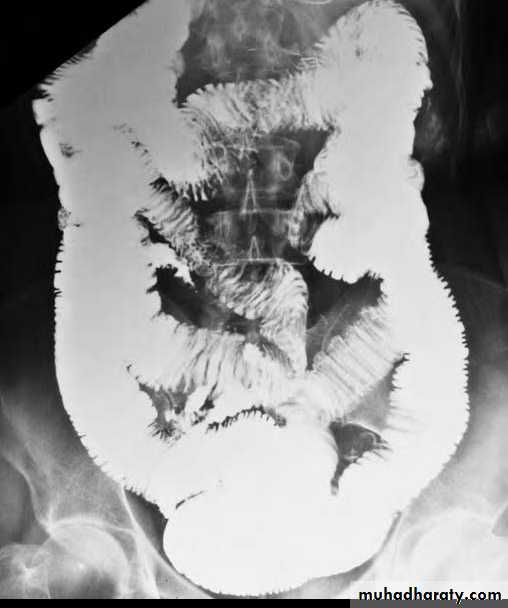

D. Ulceration SB outline is smooth apart from indentation of mucosal folds. Ulcers appear as spikes projecting outwards which may be shallow or deep.1. Crohn's disease.

Ulceration + mucosal oedema may give the appearance of cobblestone.

Multiple discrete ulcerations are present in the distal small bowel.

The central barium collections (ulcer crater) and mounds of edema are characteristic of aphthous ulcers.A cobblestone mucosal pattern affects a nonstenotic segment of small bowel